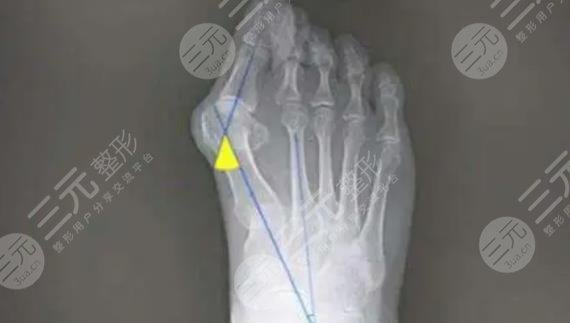

2、手術緩解

手術緩解是針對于,已經(jīng)沒有辦法采用物理方式矯正的大腳骨外翻患者,主要的實施方式。如果我們再通過了鞋子的調整和使用一些用具沒有明X果之后,并且已經(jīng)對于日常的生活產(chǎn)生了影響,就可以采用手術的方法來緩解,能夠有的改良腳部畸形狀態(tài)。

緩解大腳骨外翻的方式比較多,具體選擇哪一種方法需要根據(jù)每個人的病情去評估。在選擇方式之前,要根據(jù)患者的癥狀,通過身體的檢查和X線來綜合去判斷,不可以盲目的去選擇,因此一定要到正規(guī)的醫(yī)院,請經(jīng)驗豐富的醫(yī)生去幫助選擇和緩解。在緩解之后也要定期進行康復訓練,避免一些不良反應出現(xiàn)。